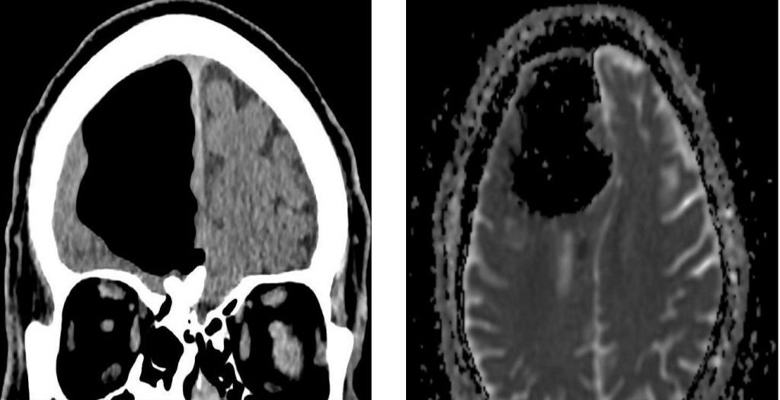

Lékaři ze Severního Irska byli při vyšetřování ohromeni v poslední době 84-letý pacient, který k nim přišel s malátností. Po provedení magnetické rezonance na hlavě muže, lékaři nečekaně zjistil, že mu chybí část pravého frontálu laloky mozku. Místo toho v lebce důchodce byl vzduch kapsa. Pak lékaři určili, že skutečný fragment mozku pacient nikam nezmizel, ale byl smíchán ve směru této abnormální dutina.